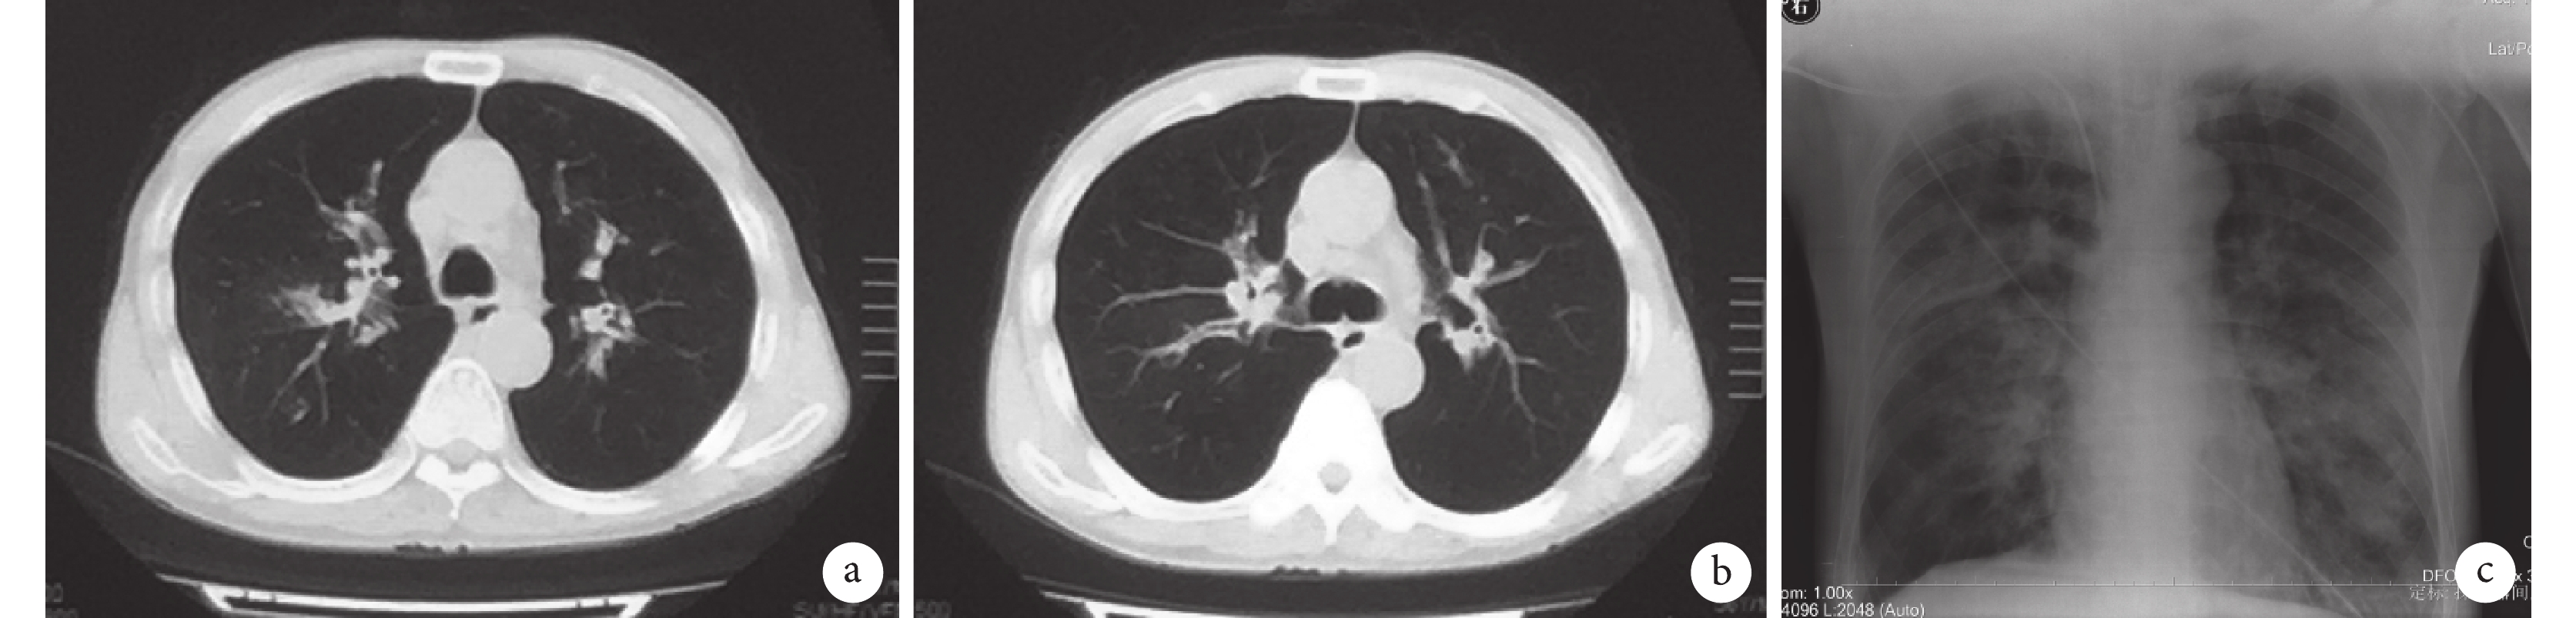

臨床資料 患者男性,56 歲,電焊工,因“咳嗽、胸悶 3 d,呼吸困難 1 d”于 2016 年 4 月 15 日入住我院呼吸內科普通病房。患者于 4 月 13 日出現咳嗽,痰不多,有胸悶,活動后明顯,至當地醫院就診,給予頭孢替安抗感染治療,患者自覺咳嗽、胸悶無緩解,漸出現呼吸困難,14 日行胸部 CT 檢查,提示雙肺斑片樣滲出(圖 1a、b),遂來我院急診,收住入院。既往有“痛風”病史 12 年,否認惡性腫瘤、器官移植、長期使用糖皮質激素及免疫抑制劑,否認吸煙。

a、b. 2016 年 4 月 14 日胸部 CT 檢查像,示雙肺散在斑片樣滲出;c. 2016 年 4 月 17 胸部 X 線檢查像,示雙肺滲出較前明顯增多

入院后給予鼻導管吸氧 5 L/min,急查動脈血氣分析示 pH 7.20,PaO2 91.4 mm Hg(1 mm Hg=0.113 kPa),PaCO2 41.7 mm Hg,BE –10.8 mmol/L,HCO3– 15.7 mmol/L,乳酸 1.1 mmol/L;血常規示白細胞計數 23.1×109/L,中性粒細胞百分比 93.9%,淋巴細胞計數 1.0×109/L,血紅蛋白 119 g/L,血小板計數 131×109/L;血 C 反應蛋白 284.62 mg/L,降鈣素原 3.85 ng/mL,1-3-β-D 葡聚糖<10 pg/mL;人類免疫缺陷病毒抗體陰性。考慮患者臨床表現與影像學不相符,嘗試使用亞胺培南 0.5 g 靜脈滴注 q8h 及常規支持對癥治療。16 日凌晨患者出現呼吸困難,意識模糊,復查動脈血氣分析 pH 7.013,PaCO2 升至 91.4 mm Hg,遂轉入呼吸科重癥監護室,緊急行氣管插管接呼吸機輔助通氣[同步間歇指令通氣模式,呼吸頻率 15 次/min,控制壓力 16 cm H2O(1 cm H2O=0.098 kPa),呼氣末正壓 6 cm H2O,吸氧濃度 60%],并給予適量補液及小劑量血管活性藥物去甲腎上腺素 0.01 μg/(min·kg)維持血壓。16 日白天多次出現呼吸機報警提示潮氣量低至 150 mL,動脈血氣分析提示 PaCO2 升高(高達 121 mm Hg)。行床邊氣管鏡檢查,鏡下見氣管、左右主支氣管及各段支氣管黏膜充血、水腫、炎癥樣改變,管腔內見大量黃白黏痰,留取痰標本送病原學培養,予以充分吸引及調整呼吸機參數后潮氣量有改觀,維持在 400 mL,結合本科室既往對相關文獻的學習,不能排除 ITBA 可能,但追問患者工作及工作場所均無吸入霉菌因素。17 日加用伏立康唑治療(第 1 天 6 mg/kg 靜脈滴注 q12h,隨后 4 mg/kg 靜脈滴注 q12h),但仍間斷出現潮氣量反復下降至 150 mL 左右,動態復查動脈血氣分析提示 PaCO2 上升(最高達 169 mm Hg),嚴重呼吸性酸中毒(pH 值最低為 6.45),胸部 X 線檢查提示雙肺沿氣管支氣管樹斑片樣滲出(圖 1c)。多次行氣管鏡吸痰處理,鏡下見黏膜潰瘍及壞死,且患者出現急性腎損傷,血肌酐為 470 mmol/L,需要大劑量血管活性藥物,去甲腎上腺素加量至 0.2 μg/(min·kg)才能勉強維持血壓(平均動脈壓 65 mm Hg)。18 日下午痰標本(16 日氣管鏡下留取)培養回報為煙曲霉(半定量 4+)(圖 2),診斷考慮為 ITBA、2 型呼吸衰竭、膿毒性休克、急性腎損傷,并加用卡泊芬凈(第 1 天 70 mg/d,然后 50 mg/d)聯合抗真菌治療。19 日開始給予床邊血液透析治療。20 日晨出現心跳驟停,搶救無效,宣布臨床死亡,家屬拒絕尸體解剖進一步明確死亡原因。

ITBA 的臨床表現無特異性,臨床癥狀包括咳嗽、咳痰、發熱、咯血,部分患者表現為呼吸困難甚至呼吸衰竭,快速進展[4]。ITBA 僅累及或主要累及氣管支氣管,影像學早期可能僅表現為氣管支氣管管壁增厚,隨著曲菌的侵襲及疾病的進展,胸部影像學可出現結節、實變,甚至空洞形成,但這些均非 ITBA 特征性影像學改變,故胸部影像學對于 ITBA 診斷價值不大[6]。本例患者發病初期僅表現為咳嗽、胸悶,快速進展為呼吸困難及呼吸衰竭,后誘發膿毒性休克,且初始胸部 CT 無明顯重癥感染征象,病情進展后胸部 X 線檢查提示雙肺斑片樣滲出,若無豐富臨床經驗,單純從臨床表現及影像學確實難以做出準確判斷。